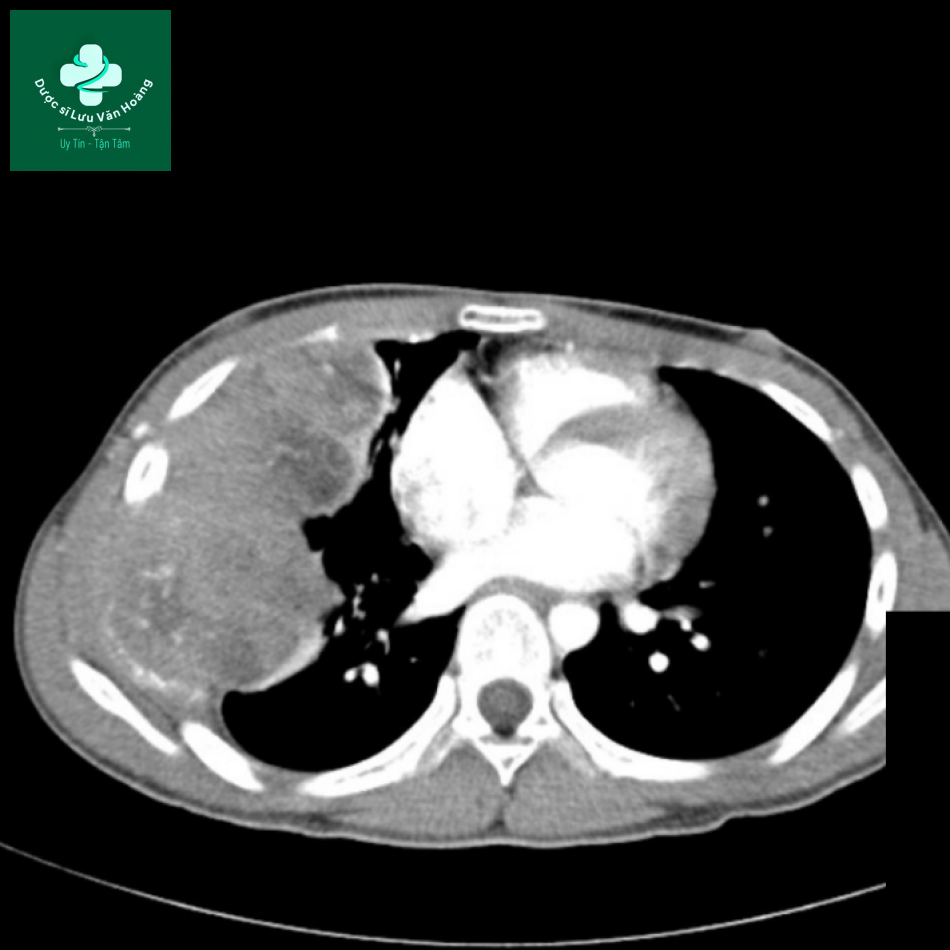

CT cho thấy một khối rất lớn, mất lớp mỡ ngoài màng phổi. Bệnh nhân được chẩn đoán là sarcoma Ewing thành ngực hay u Askin.